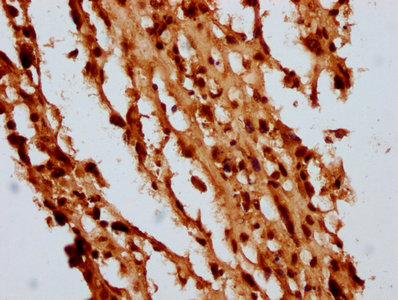

IHC image of CSB-PA010429OA05nbhbHU diluted at 1:10 and staining in paraffin-embedded human melanoma performed on a Leica BondTM system. After dewaxing and hydration, antigen retrieval was mediated by high pressure in a citrate buffer (pH 6.0). Section was blocked with 10% normal goat serum 30min at RT. Then primary antibody (1% BSA) was incubated at 4°C overnight. The primary is detected by a biotinylated secondary antibody and visualized using an HRP conjugated SP system.